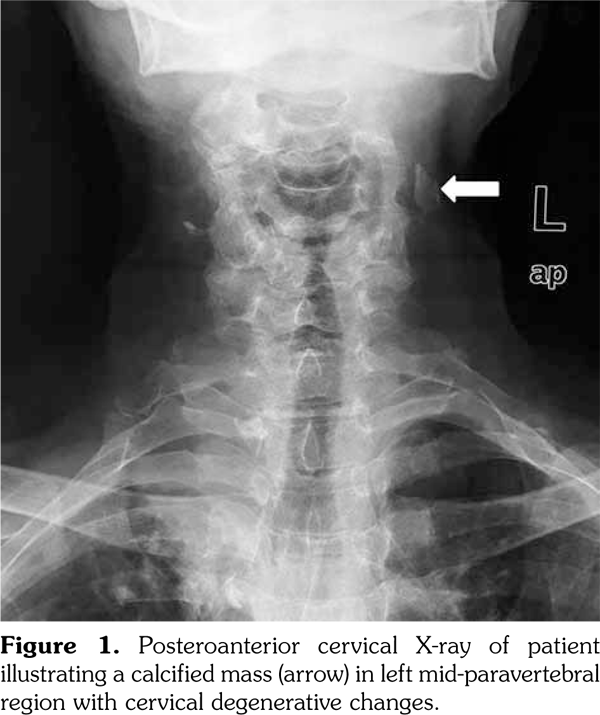

An 80-year-old female patient was examined due to complaint of neck pain over the last year which has aggravated recently. She denied history of trauma. Her medical history indicated that she was taking some medications for hypertension and coronary artery disease. Physical examination was compatible with cervical osteoarthritis with limited cervical range of motion in all directions and tenderness to palpation. Laboratory findings including complete blood count, erythrocyte sedimentation rate, C-reactive protein, serum calcium, phosphorus, parathyroid hormone, and vitamin D levels were within normal ranges. On radiological evaluation, cervical X-ray revealed a calcified mass in the left mid-paravertebral region with cervical degenerative changes (Figure 1). At first glance, a calcification inside the cervical muscles was suspected. Ultrasonographic examination of the cervical region revealed the presence of intraluminal calcification at the level of the bifurcation of the left common carotid artery (Figure 2a-c). The patient was referred to neurology department for being at risk for stroke.

Carotid arteries are the major vascular structures that deliver blood to brain. A blockage in carotid arteries can lead to stroke which is typically caused by atherosclerosis.(1) The artery-wall thickens as a result of invasion and deposit of white blood cells and proliferation of intimalsmooth-muscle cell creating a fatty plaque which is known as atherosclerosis.(2) These deposits also contain cellular waste, cholesterol, and triglycerides with often occurring calcification.(2) Therefore, paravertebral calcifications seen on X-ray might be inside the vessels, particularly in the elderly. Complications of the carotid artery calcification should be kept in mind, so that the patient can be referred to the relevant departments before occurrence of catastrophic consequences such as stroke. Ultrasonography should be the method of choice in confirming the diagnosis.(3)